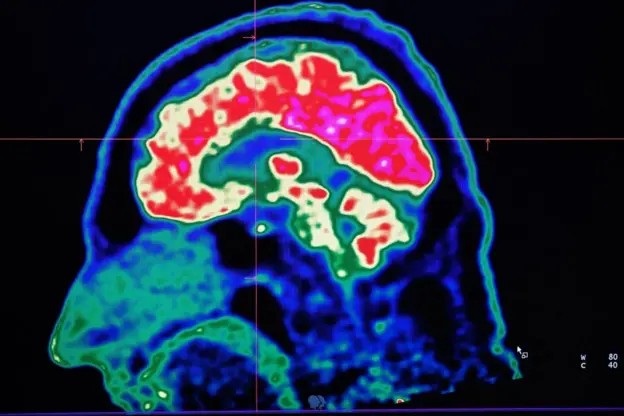

A Síndrome de Dravet é apenas uma das muitas doenças neurológicas que se agravam com o aumento das temperaturas, diz Sanjay Sisodiya, da University College London, um dos pioneiros no estudo dos impactos das mudanças climáticas sobre o cérebro.

Ao se aprofundar na literatura científica, Sisodiya descobriu uma série de condições neurológicas que são agravadas pelo aumento da temperatura e da umidade, incluindo epilepsia, acidente vascular cerebral (AVC), encefalite, esclerose múltipla, enxaqueca, entre outras.

Ele também identificou que os efeitos das mudanças climáticas sobre o cérebro humano já estão se tornando visíveis.

Durante a onda de calor que atingiu a Europa em 2023, por exemplo, cerca de 7% das mortes adicionais estavam relacionadas diretamente a problemas neurológicos.

Percentuais semelhantes foram vistos durante a onda de calor no Reino Unido em 2022.